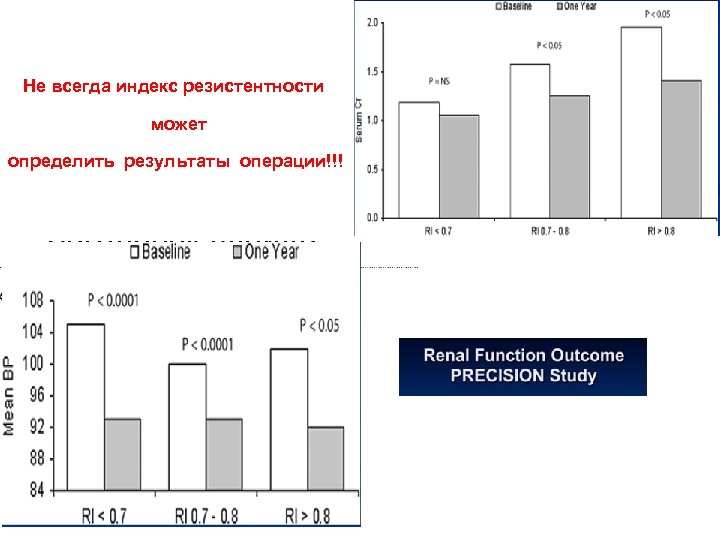

Не всегда индекс резистентности может определить результаты операции!!!

Не всегда индекс резистентности может определить результаты операции!!!